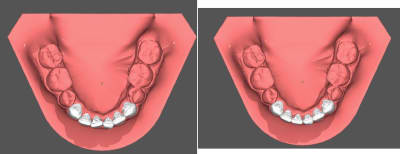

Et petit suivit d'un cas collé il y a sept semaine ( page deux sur ce fil ) .

Après deux semaines ça ne bougé pas trop donc je suis passé au niti 14 en bas il y a deux semaine et tout d'un coup c'est aller beaucoup mieux. En haut c'est toujours du niti 12.

Juste pour rappelle j'ai juste prit une empreinte alginate la patiente n'étant pas sure de l'option choisie ( céramique ou lingual ) et ai fait le labo sur deux jours.

Les 2D ça enfonce invisalign pour les cas simple que ce soit au niveau de la rapidité pour débuter le traitement , les cout labo ou l'expérience pour le patient.